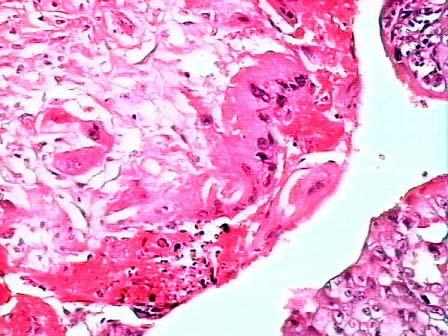

问题 女性,24岁,经产妇,曾患葡萄胎。因阴道不规则流血行妇检,见阴道前后壁数个紫红色结节,尿HCG(+)。手术切除子宫,见表面数个蚕豆大小结节,有溃烂,切面呈紫红色,边界不清已侵及肌层和浆膜。镜下见明显出血坏死的病灶中有明显异型的肿瘤细胞,呈条索状或片状排列,未见间质、血管及绒毛结构(如图)。免疫组化示HCG阳性(如图),应诊断为 ( )

选项 A.子宫绒毛膜上皮癌 B.子宫平滑肌瘤 C.子宫平滑肌肉瘤 D.子宫内膜间质结节 E.子宫内膜腺癌

答案 A